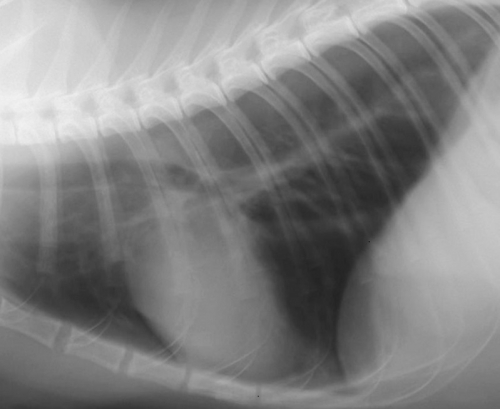

下2枚の写真は同じ犬の胸部レントゲン写真です。どちらも黄色の丸の中に白い円形の何かが見えると思います。

実はこの写真は肺転移した腫瘍のパターンなのですが、上のCRより下のDRの画像の方がよりはっきりと異常を確認できます。どちらも同じデジタルレントゲンなのですが、異常を際立たせるという意味でもDRに優位性があります。